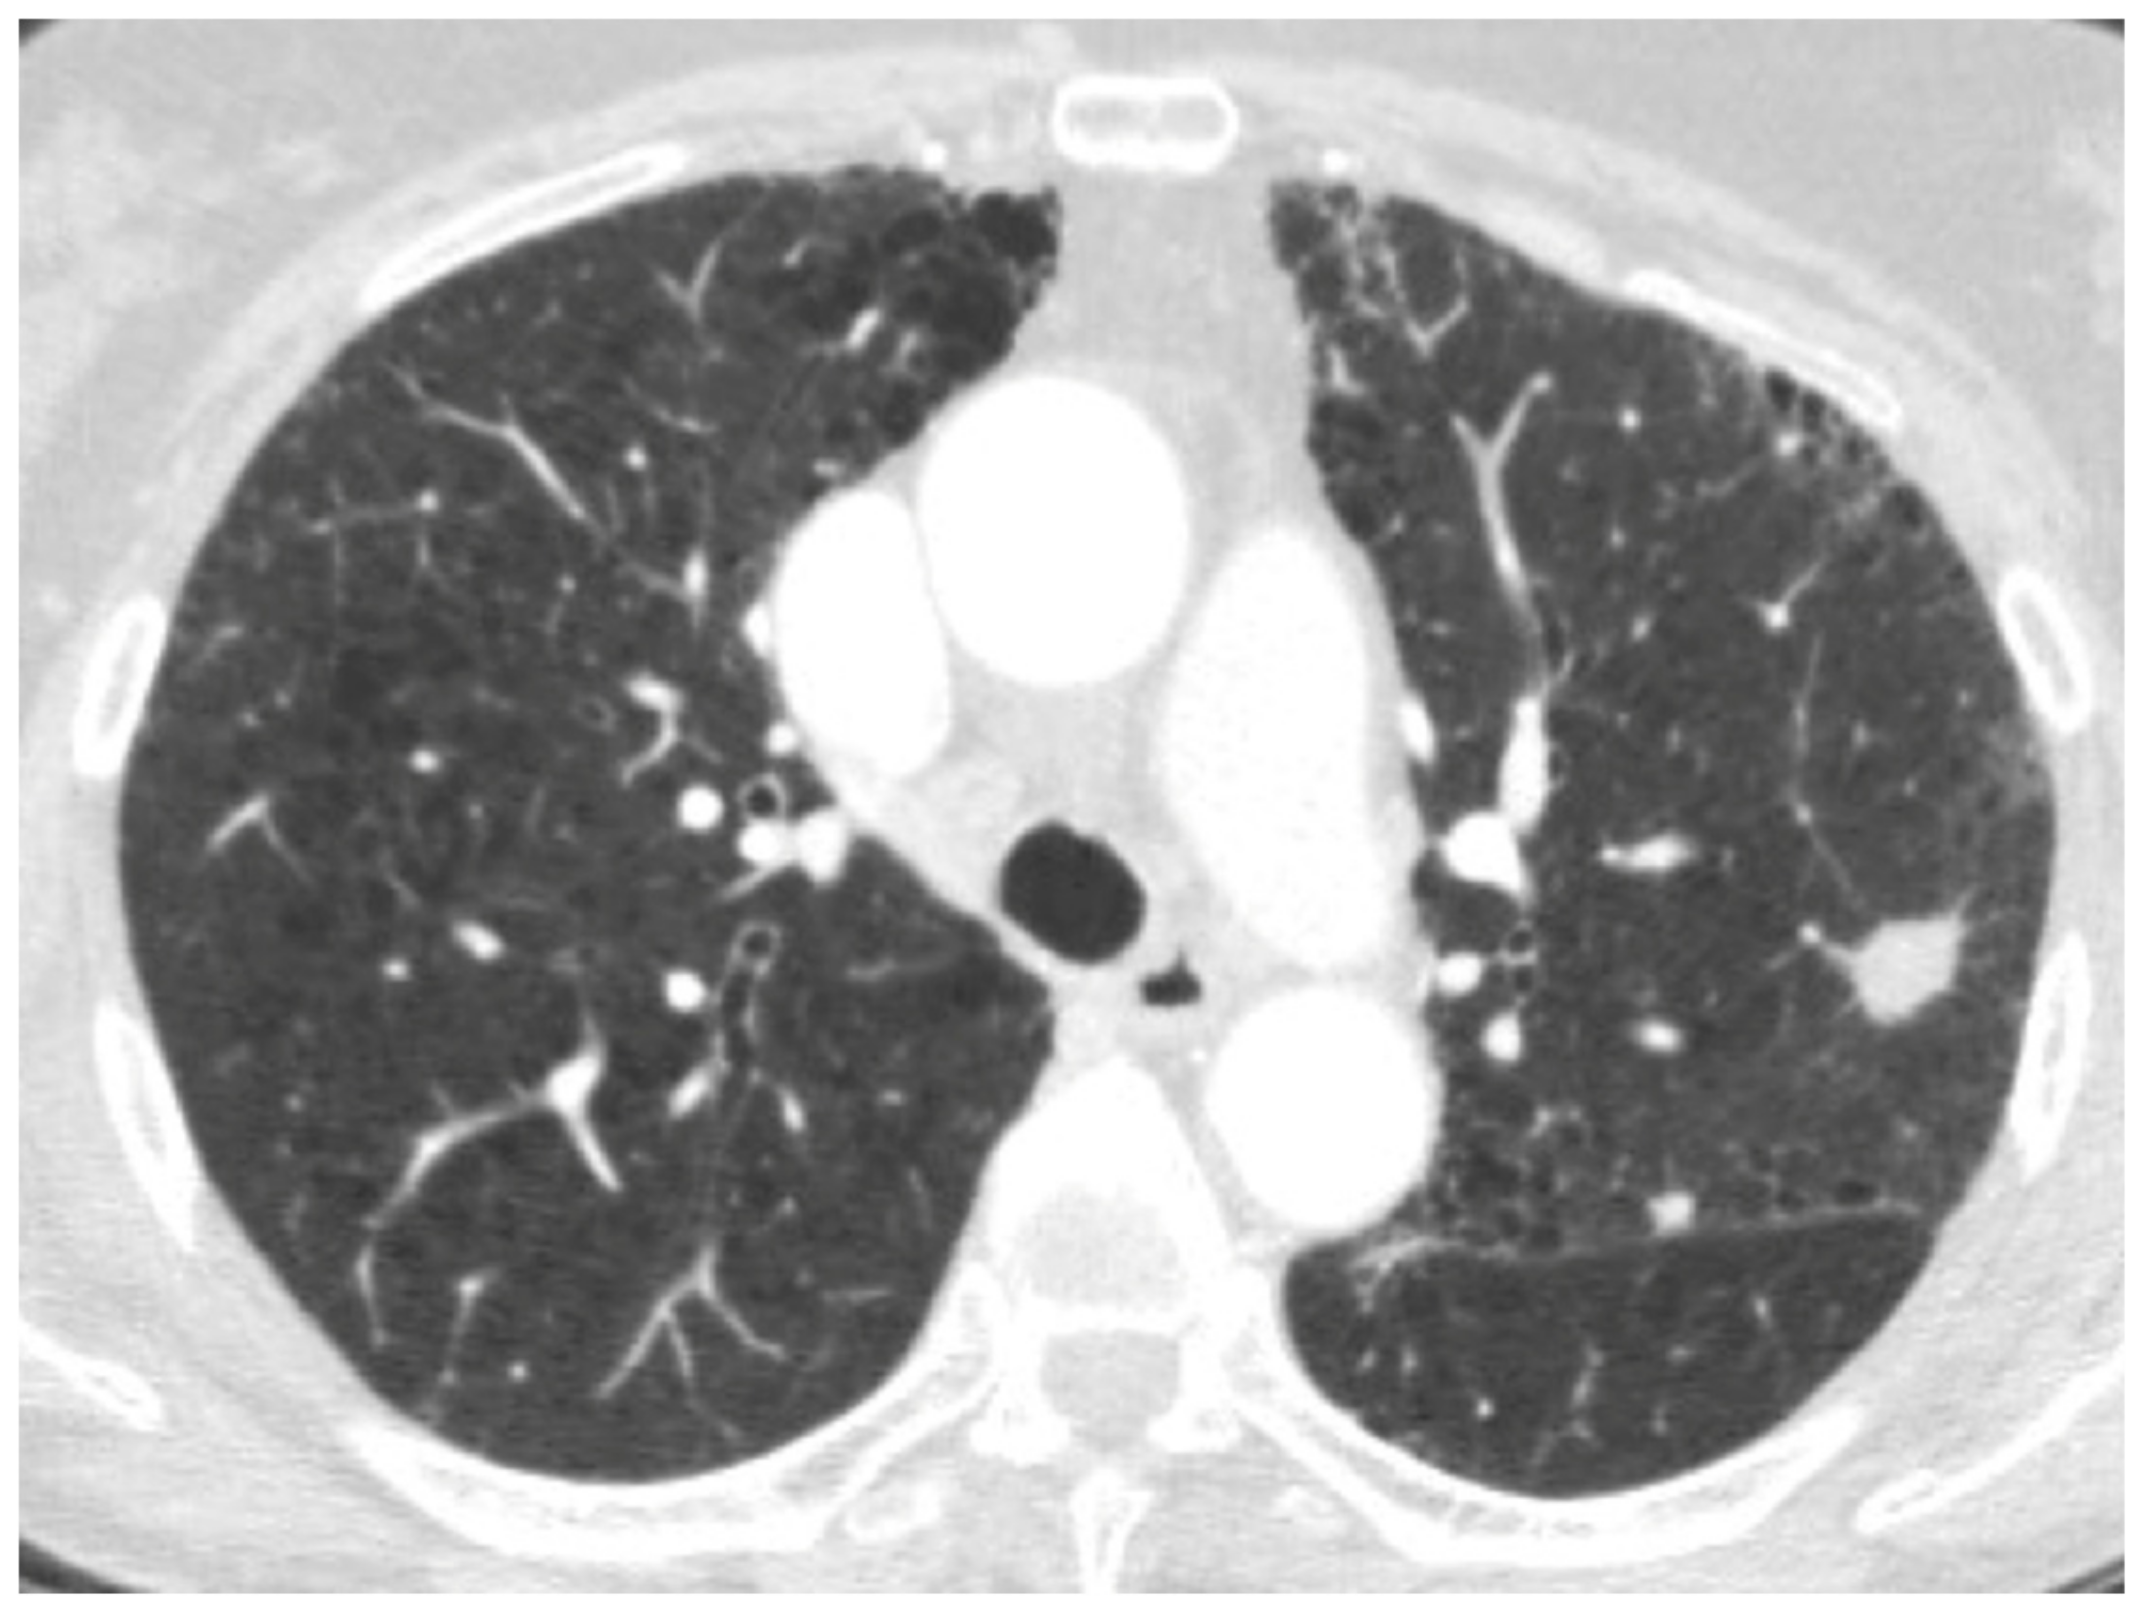

| Acute exacerbation IPF | New bilateral ground glass opacities and/or consolidation on a background of reticular or honeycombing pattern. | ||

| Right heart failure | Profuse septal thickening, ground glass opacities, pleural effusion on a background of reticular or honeycombing pattern. | ||